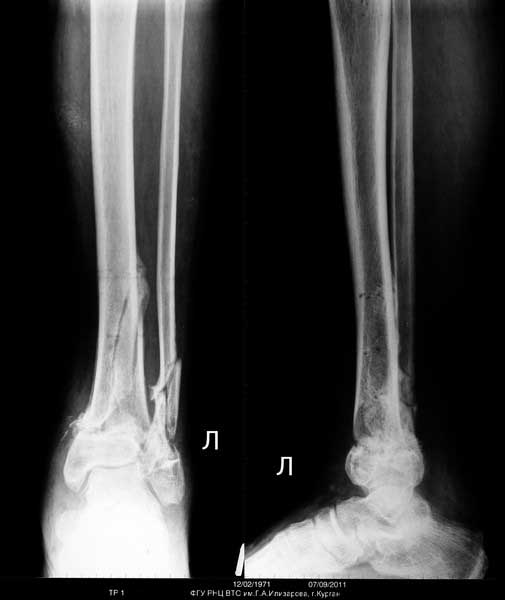

Выставляю случай не менее тяжелый. Фиксация в аппарате Мацукидиса-Шевцова 83 дня, общий срок нетрудоспособности 112 дней. Никаких проблем с остеосинтезом и с последующим лечением не было. Никаких воспалений мягких тканей. 3 перевязки за весь период лечения.Главное - захотеть.